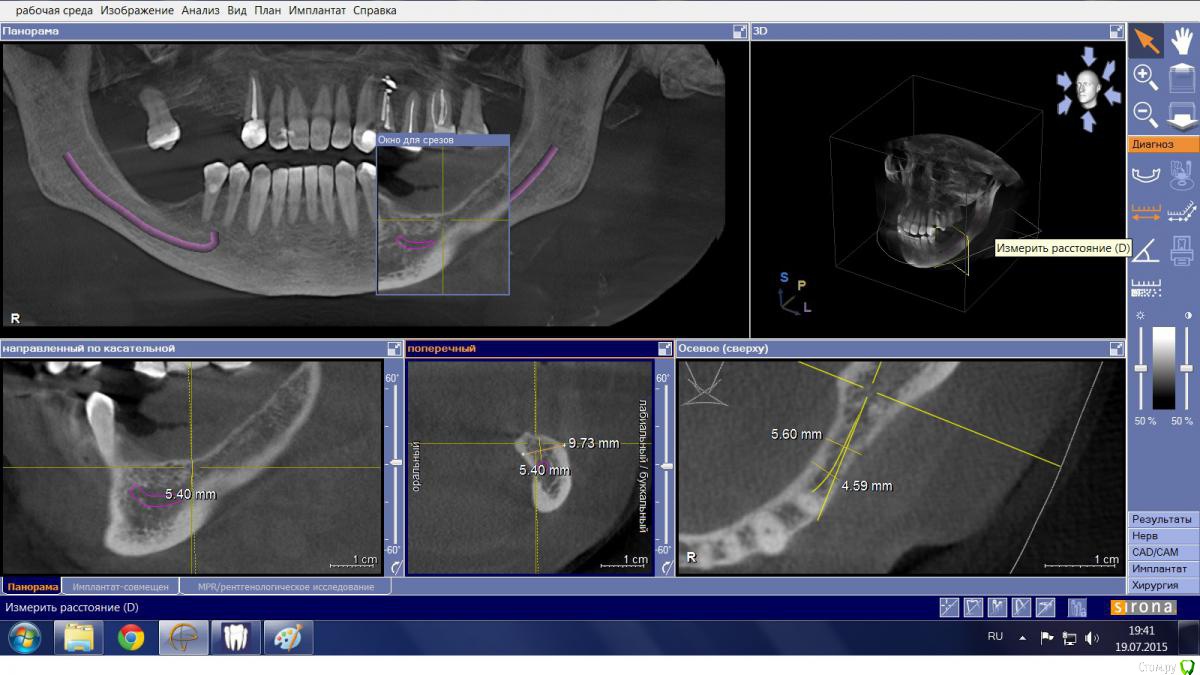

Mario Опубликовано 19 июля, 2015 Поделиться Опубликовано 19 июля, 2015 Здравствуйте, доктора, есть пациентка, категорически не желающая носить съемный протез и опыта такого не имеющая. Думал в сторону "крыши", но тут где-то ILGAMSA, кажется, писал, что не менее 5 мм крыша + 1 мм до канала, иначе резорбция. Латерализацию не рассматривал ввиду отсутствия соответствующего скилла. Какие еще могут быть варианты? Ссылка на комментарий

Mario Опубликовано 19 июля, 2015 Автор Поделиться Опубликовано 19 июля, 2015 Лучше отвертикалитьширина гребня в области 35 позволит? Ссылка на комментарий

АнтонТЛТ Опубликовано 19 июля, 2015 Поделиться Опубликовано 19 июля, 2015 Мпк особо не сработает. Сетка, цитопласт, Кури Ссылка на комментарий

Bier Опубликовано 19 июля, 2015 Поделиться Опубликовано 19 июля, 2015 МПК тут не подойдет. Если только создать вертикальный каркас минипластиной.Я бы однозначно не выбирал тут блок, т.к. итак моноблоки по вертикали работают плохо, так тут еще и основание очень узкое.GBR - чем создатите каркас, решать Вам. Способов много. Ссылка на комментарий